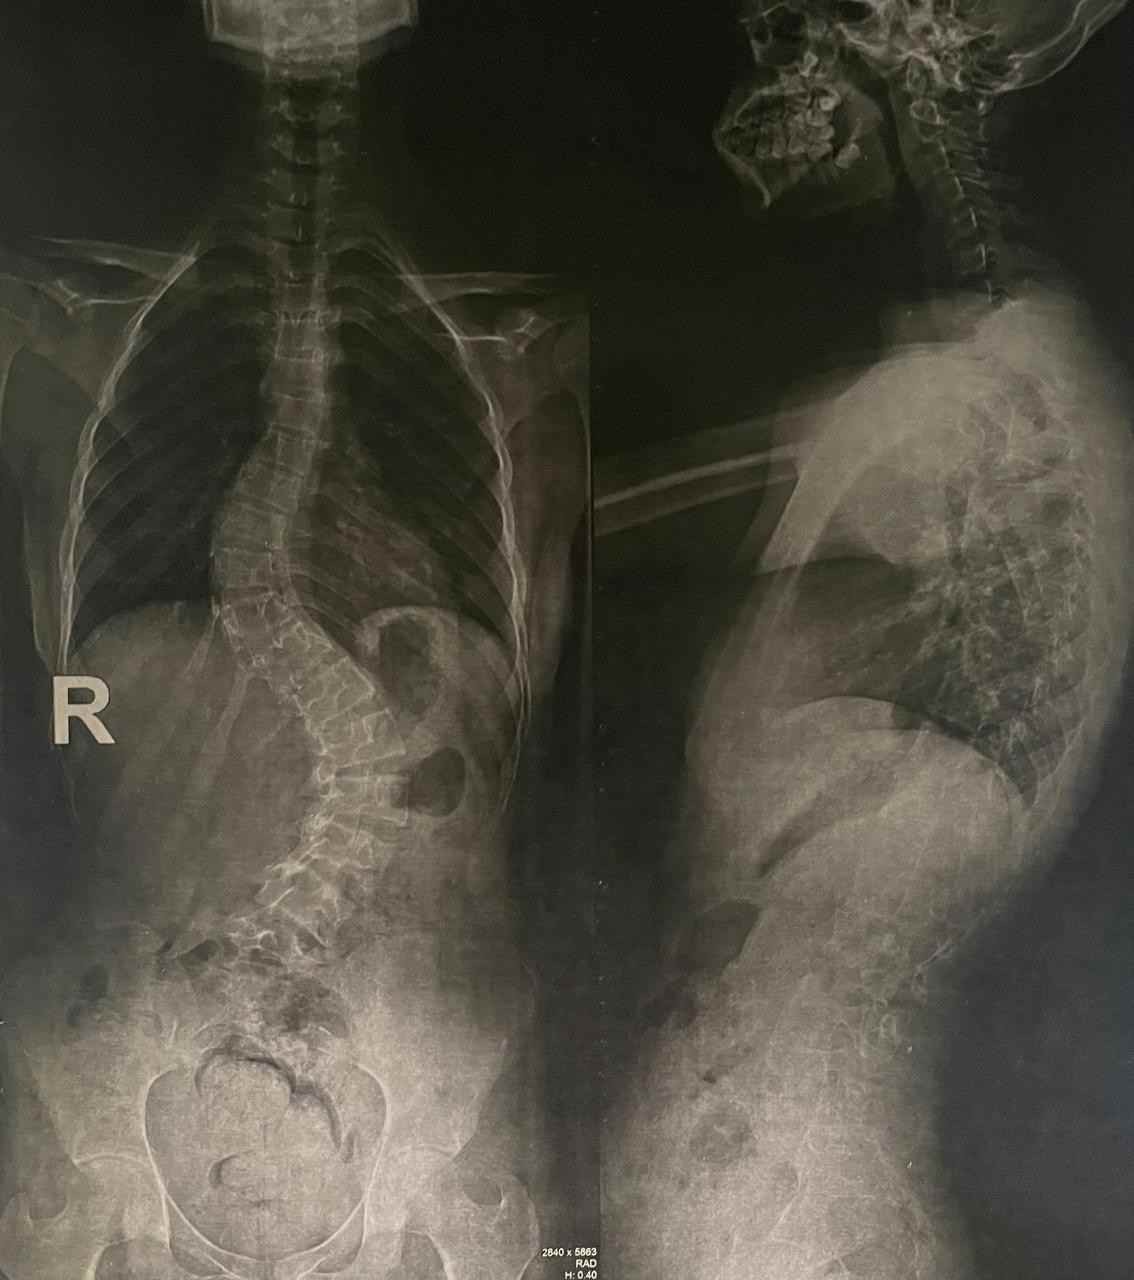

اعوجاج مزدوج بالفقرات الصدرية و القطنية

double curvature of the thoracic and lumbar vertebrae

An advanced corrective surgery was performed to treat double curvature in thoracic and lumbar vertebrae. This condition involves abnormal curvatures in both the chest and lower back areas of the spine, affecting posture, movement, and causing chronic pain.

Key Symptoms of the Condition

• Visible curvatures in multiple back areas

• Chronic pain in middle and lower back

• Asymmetry in shoulder and pelvic levels

• Difficulty maintaining straight posture

• Rapid fatigue when sitting or standing

• Breathing difficulties in advanced cases